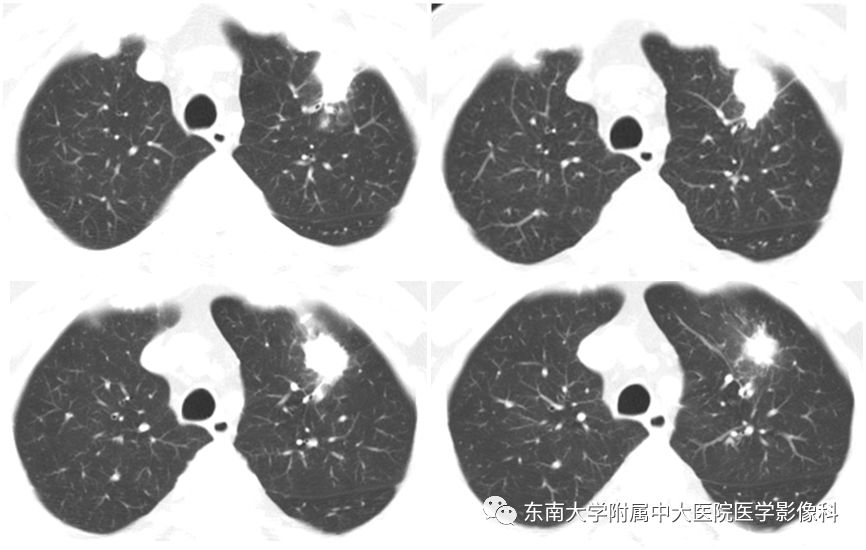

病史

男,66岁,因“咳嗽、咳痰7天”入院

病例结果:病例1:机化性肺炎;病例2:肺腺癌